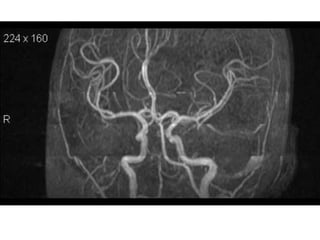

3D TOF is now accepted as a non-invasive screening tool for

familial aneurysmal disease.

Sensitivity is greater for detecting aneurysms > 3mm (94%) than

aneurysms < 3mm (38%). ( White et al 2000)

Overall inferior to DSA and misses aneurysm <3mm.(Adams et al

2000)

3D CE MRA is superior to TOF MRA .It is method of choice for

evaluation of giant cerebral aneurysms.

CE MRA shows promise in the follow-up of treated intracranial

aneurysms.

Aneurysms